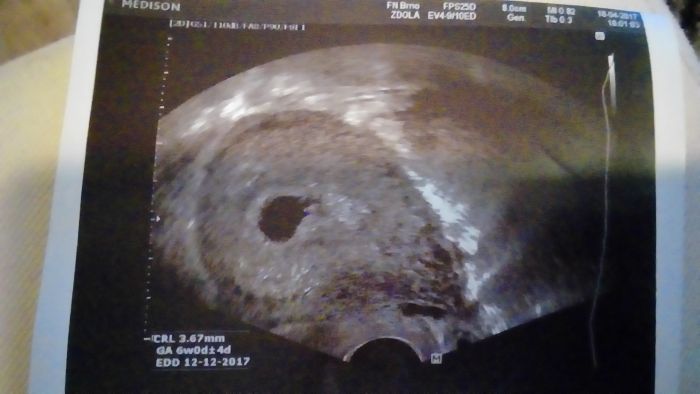

Tak srdicko bylo a BILO ? Podle kalkulacky na netu jsem dneska 7+3, ale podle utz u dr. jsem 6+4. K poceti tedy doslo pozdeji. Za 3 tydny kontrola. Mam velikanskou radost, ale jak dr. rikal, jeste nemame vyhrano. Nicmene mi uz rezervoval termin na prvotrimestialni screening a ja si pak jeste pro jistotu vyzadala neinvazivni prenatalni vysetreni z krve, kterou posilaji do USA a stoji to 13tis. Ale to za to dame, uz kvuli memu veku!